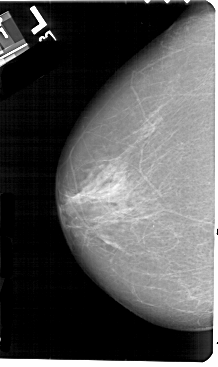

A_1574_1.LEFT_MLO

LEFT_MLO LINES 5491 PIXELS_PER_LINE 3406 BITS_PER_PIXEL 12 RESOLUTION 43.5 NON_OVERLAY